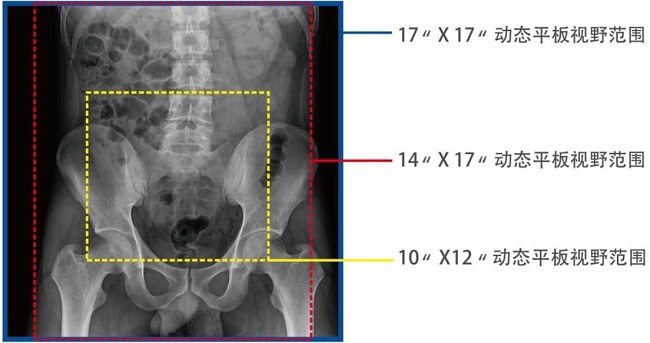

17*17英寸的超高清像素動(dòng)態(tài)平板探測(cè)器,更大的視野范圍,能對(duì)胸部腹部等部位實(shí)現(xiàn)大范圍全覆蓋,動(dòng)靜態(tài)之間無(wú)感切換。透視檢查無(wú)須對(duì)患者重新定位便可觀察到足夠大的人體器官組織,避免漏診誤診。

大尺寸動(dòng)態(tài)平板技術(shù),覆蓋檢查面積范圍廣,輕松實(shí)現(xiàn)胃十二指腸等大面積造影,無(wú)需移動(dòng)即可觀看整個(gè)動(dòng)態(tài)過(guò)程,避免噪點(diǎn)對(duì)圖像的影響。